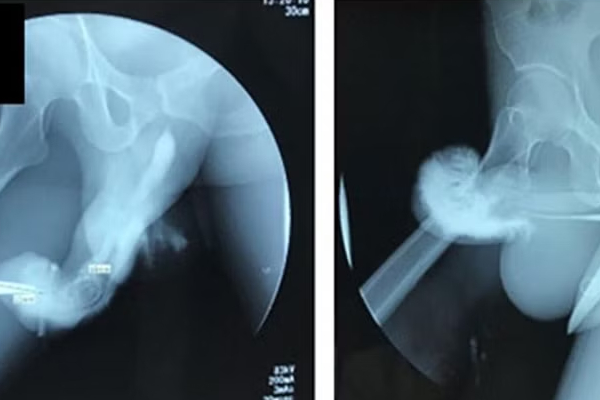

இந்தோனேசியாவைச் சேர்ந்த ஒருவர் வித்தியாசமான முறையில் உடலுறவு மேற்கொண்டபோது தனது ஆணுறுப்பில் எலும்பு முறிவு ஏற்பட்டுள்ளது.

இந்தோனேசியாவில் 37 வயது நபர் தனது துணைவருடன் ரிவர்ஸ் கவ் கெர்ள் (Reverse Cowgirl) என்ற பொசிஷனில் பாலியல் உறவில் ஈடுபட்டார். அப்போது அவரது ஆணுறுப்பில் முறிவு ஏற்பட்டதாக கூறப்படுகிறது. அவரது ஆணுறுப்பில் இருந்து ரத்தம் வந்துள்ளது.

அவரால் சிறுநீர் கழிக்க முடியாத நிலை உருவாகியிருக்கிறது. இதனால் அந்த நபர், உடனடியாக மருத்துவமனையில் அனுமதிக்கப்பட்டுள்ளார். அவருக்கு உடனடியான அறுவை சிகிச்சை மேற்கொள்ளப்பட்டுள்ளது. முதல் 3 நாள்கள் தீவிர சிகிச்சை பிரிவில் சிகிச்சை பெற்று வந்துள்ளார். காயம் குணமாகும் வரை சிறுநீர் கழிக்க அவருக்கு catheter முறையில் டியூப் பொருத்தப்பட்டது.